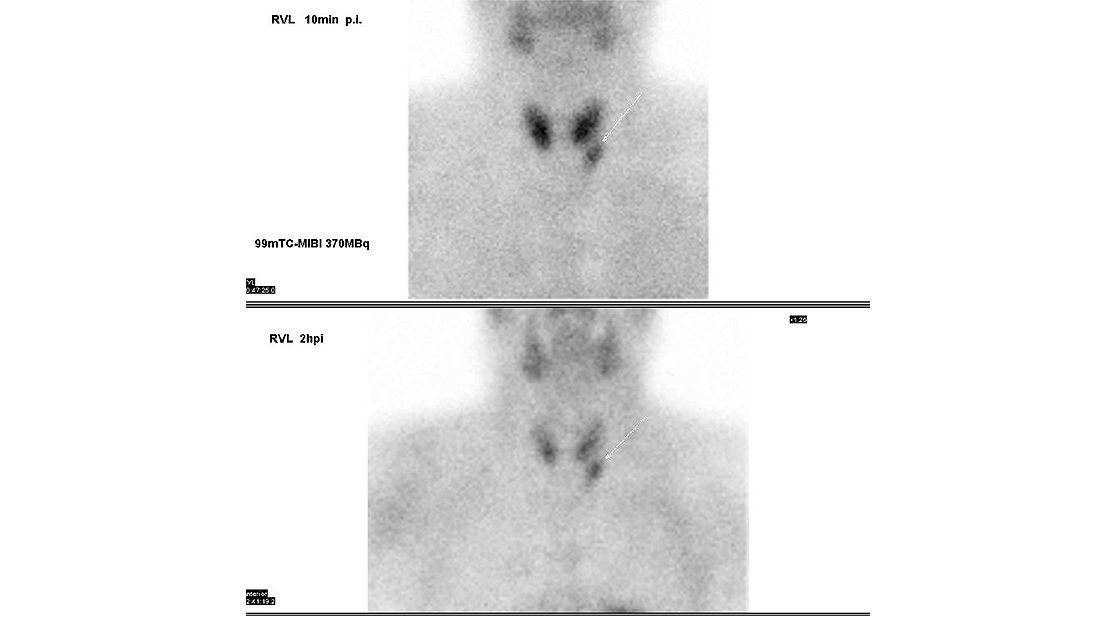

Zehn Minuten später kann die eigentliche Untersuchung beginnen. Dafür platzieren wir den Patienten auf der Untersuchungsliege liegend. Die Gamma-Kamera hält dann fest, wie sich das radioaktive Medikament in den Nebenschilddrüsen verhält. Dieses erste Szintigramm dauert 10 Minuten.

Nach 1 bis 1,5 Stunden Wartezeit, in denen der Patient die Räume der Nuklearmedizin auch verlassen kann für einen Spaziergang oder einen Kaffee, werden weitere Aufnahmen gemacht, wieder liegend.

Mit einer SPECT/CT-Untersuchung erhalten wir eine errechnete 3D-Darstellung. Zusätzlich machen wir ein weiteres Szintigramm. Insgesamt dauern die beiden Untersuchungen etwa 30 Minuten, in denen der Patient ruhig liegen sollte.